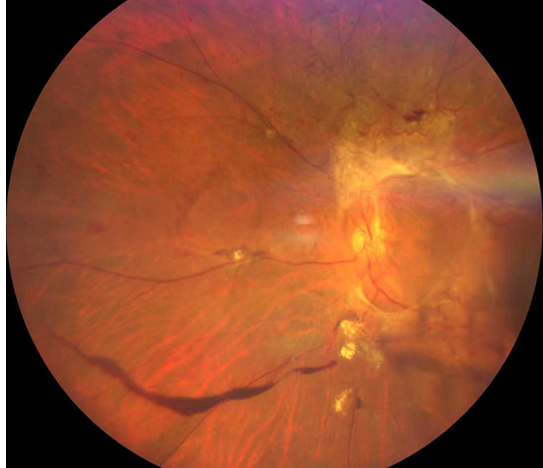

厦门眼科中心的检查结果让全家倒吸一口凉气:

右眼视力0.05,左眼仅余眼前光感;

双眼被确诊为Ⅱ期增殖性糖尿病视网膜病变(以下简称“糖网”),并伴有黄斑水肿。

糖尿病视网膜病变

这意味着,如果再晚来几天,视网膜损伤将不可逆转,他将永远失去光明。

万幸,眼底病科王晓波主任为郑先生实施了左眼25G微创万速玻璃体切割手术联合抗VEGF药物注射治疗,手术很顺利。术后郑先生左眼视力逐渐恢复到0.5。